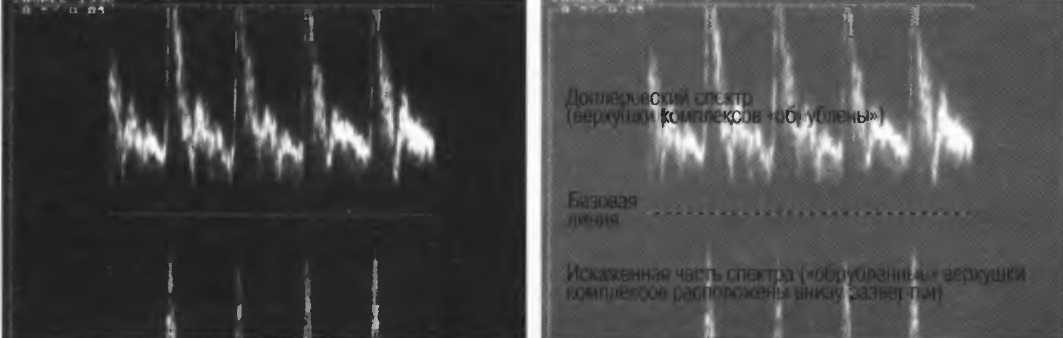

2. В импульсном режиме доплерографии ультразвук излучается импульсами с хорошим разрешением по глубине. При этом имеется возможность избирательного измерения скорости кровотока в отдельном сосуде (рис. 2а). Недостатком данного режима является невозможность измерения высоких скоростей потока в глубокорасположенных сосудах, а также возможность искажения спектра скоростей кровотока, когда высокоскоростные потоки ошибочно изображаются как низкоскоростные.

Рис.2б. Артефакт искажения доплеровского спектра: пик скорости каждой волны расположен ниже базовой линии, определяя этим наличие потока в противоположную сторону. Этот артефакт возникает, когда частота повторения импульса недостаточна для измерения высоких скоростей движения отражающих структур.